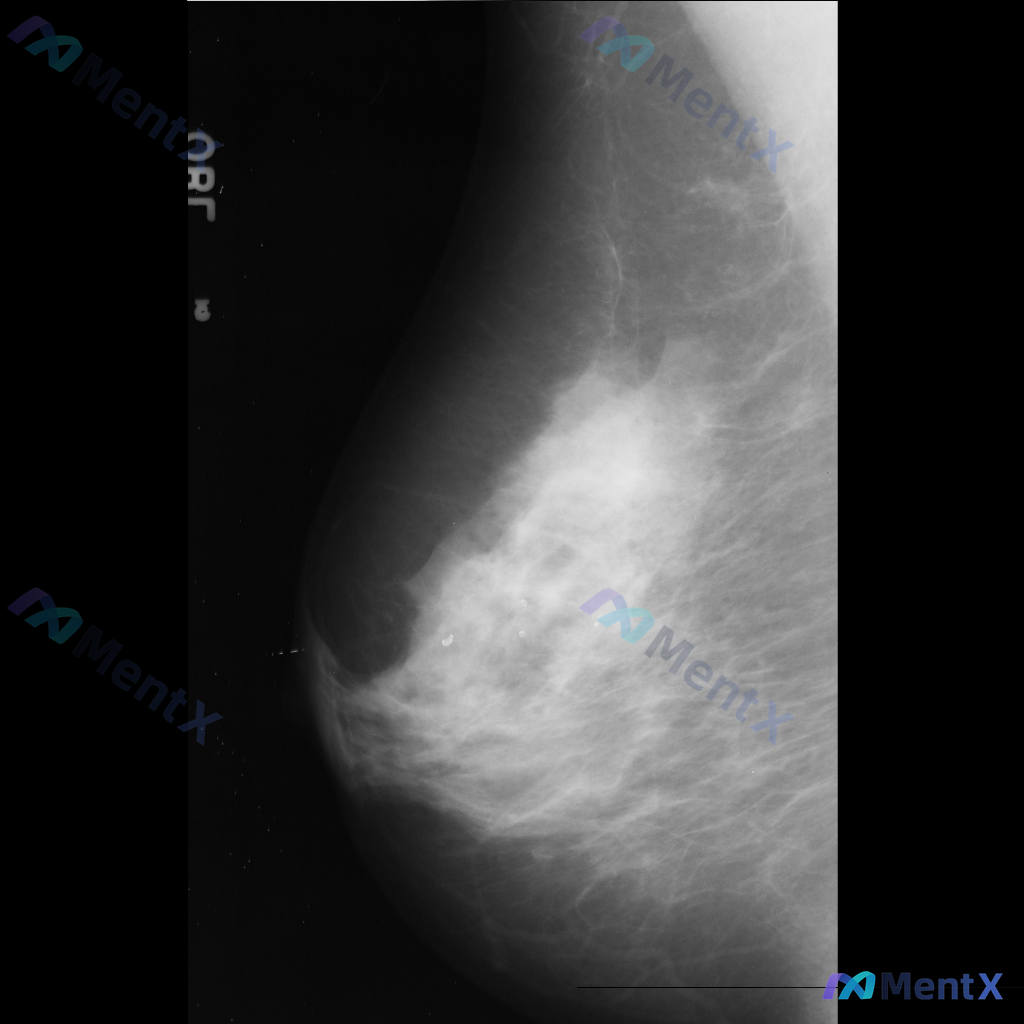

整理到一张乳腺钼靶影像的描述资料,想请大家帮忙看看更倾向哪种情况。 【基本影像背景】 - 检查侧:右侧乳腺 - 乳腺构成:不均匀致密型(BI-RADS C型) 【影像异常发现】 - 右侧乳腺见一处不规则形高密度肿块 - 肿块边缘呈毛刺状或星芒状 - 局部伴有显著的结构扭曲 - 无明确钙化灶显示 -...